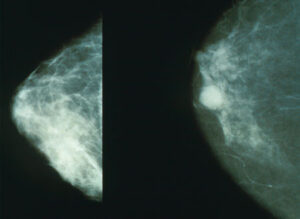

Correlazione tra dimensioni del seno e rischio cancro

Pare vi sia una correlazione genetica tra le dimensioni della mammella e il rischio di tumore al seno. Lo studio...